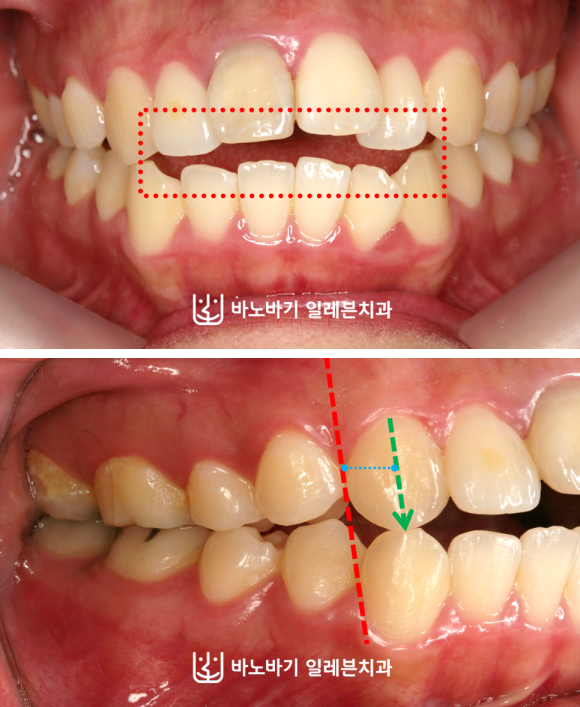

이밖에 앞니가 잘 닿지 못하며, 상악 우측 치열만 앞으로 나왔다는 점을 발견했습니다.

이런 점이 올바른 저작활동에 방해요소로 작용하였습니다. 이점을 십분 고려하면서 무턱교정이 이루어졌습니다.

이렇게 무턱교정이 끝났습니다. 전치부 개방교합을 해소하여 앞니가 닿을 수 있게 됐고, 중심선 불일치도 해결했습니다.

우측 치열도 교합을 맞춰서 정상적인 모습으로 치아가 맞물리도록 만들었습니다. 그만큼 저작기능도 좋아졌죠.

이번 사례에서는 어떤 수술도 이루어지지 않았습니다. 상악 앞니의 전방경사를 적절한 수준으로 조정하면서, 전치부를 뒤로 움직였는데요.

이런 과정만으로 돌출입이 상당 부분 개선되었습니다. 윗니와 아랫니의 앞뒤간격도 굉장히 많이 줄어들었네요.

옆모습도 많이 좋아졌습니다. 입술이 자연스레 다물어지도록 만드는 데에 성공했습니다.

억지로 힘을 줄 필요가 없어 입을 다문 모습이 훨씬 더 편안한 것처럼 보였습니다.

평소에 입으로 숨을 쉬는 구호흡 습관이 사라졌으며, 호두턱도 나타나지 않았습니다.